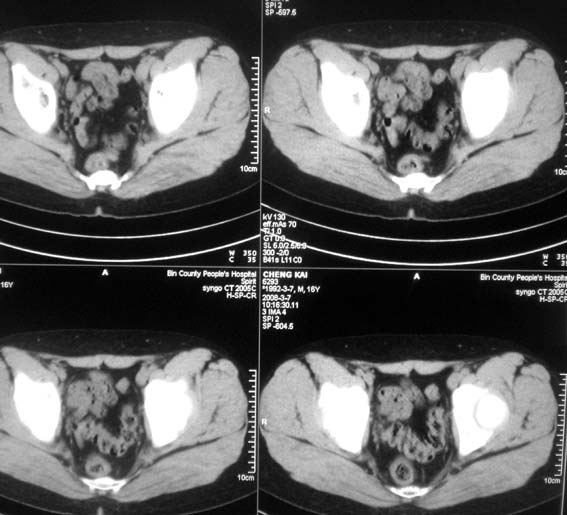

标题: CT12101:髋关节疼痛,请会诊。

男,16岁,髋部疼痛,发育延迟。

考虑:双侧髋臼发育不良性骨病。

双侧髋臼发育不良性骨病

双侧髋臼发育不良性骨病.股骨头早期坏死?

双侧髋臼发育不良性骨病(髋臼窝变浅,髋臼内上缘关节面毛糙)。